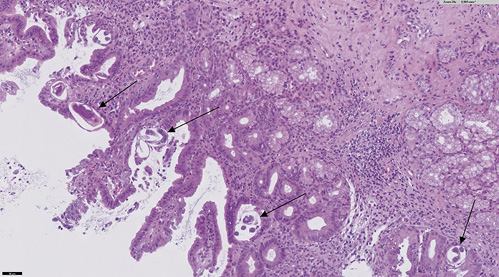

An abdominal computed tomography was performed (without intravenous contrast because the patient was allergic). It showed dilation of the second and third duodenal portions, with wall thickening and rarefaction of the adjacent fat, in relation to inflammatory changes that seemed to affect a segment of about 5 cm (Fig. 2). Symptoms persisted, so a magnetic enteroresonance was done and mild dilation and slight inflammatory changes were found which affected a segment of about 3 cm of the second duodenal portion. The involvement seemed to have improved since the previous computed tomography. The histological study of gastric and duodenal biopsies showed colonization of acini by S. stercolaris in both the antrum and the duodenum (Fig. 3). A stool test confirmed infection with this parasite. Treatment of S. stercolaris hyperinfestation with ivermectin and albendazole was initiated, with progressive tolerance and clinical improvement. She completed 18 days of treatment with antihelminthic drugs until repeated stool tests showed no presence of the parasite. Five months later the patient had a new exacerbation of acquired thrombotic thrombocytopenic purpura, which was treated again with glucocorticoids, plasma exchange, and rituximab, but did not show any gastrointestinal symptoms and stool tests remained negative with prophylaxis with ivermectin.